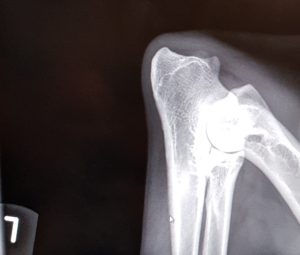

Endnu 2 hunde er blevet bedømt af DKK og fundet HD, AD og OCD frie, vi er så glade og stolte!